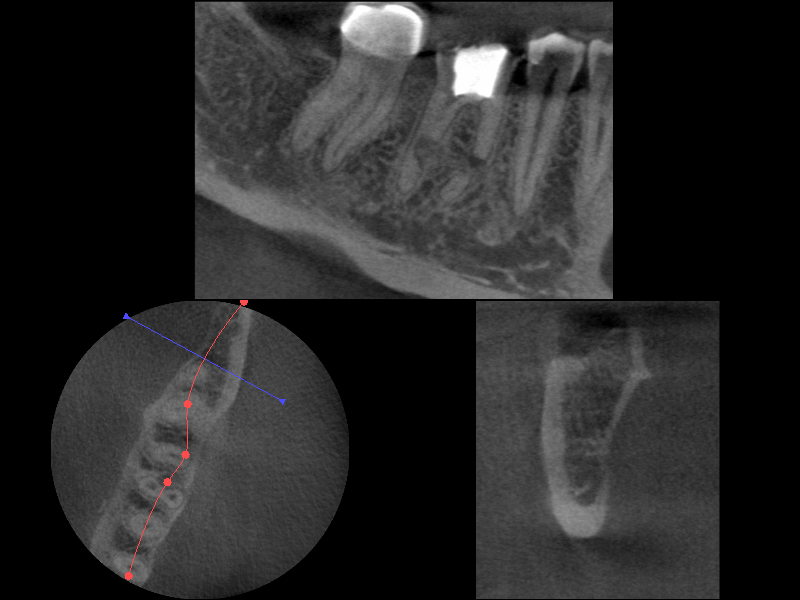

02 – Zahn 46 – 3DSlice 1

Wurzelresorption mal anders